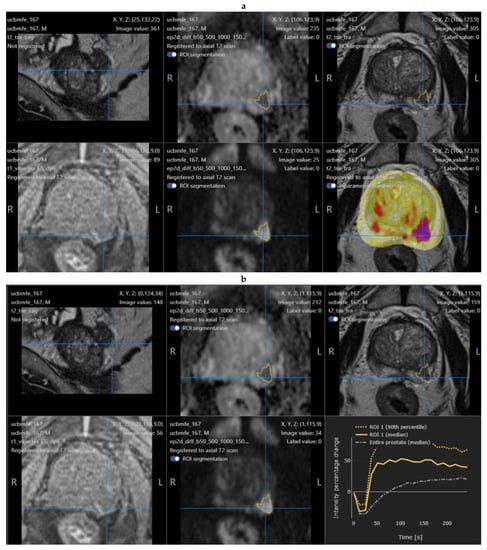

2.4. Quantib Prostate Software

- The multiparametric MRI analysis, where standardized assessment of MRI includes the ability to add, edit, and inspect ROIs and score them according to PI-RADS general scoring, finding, reviewing, and approving the results;